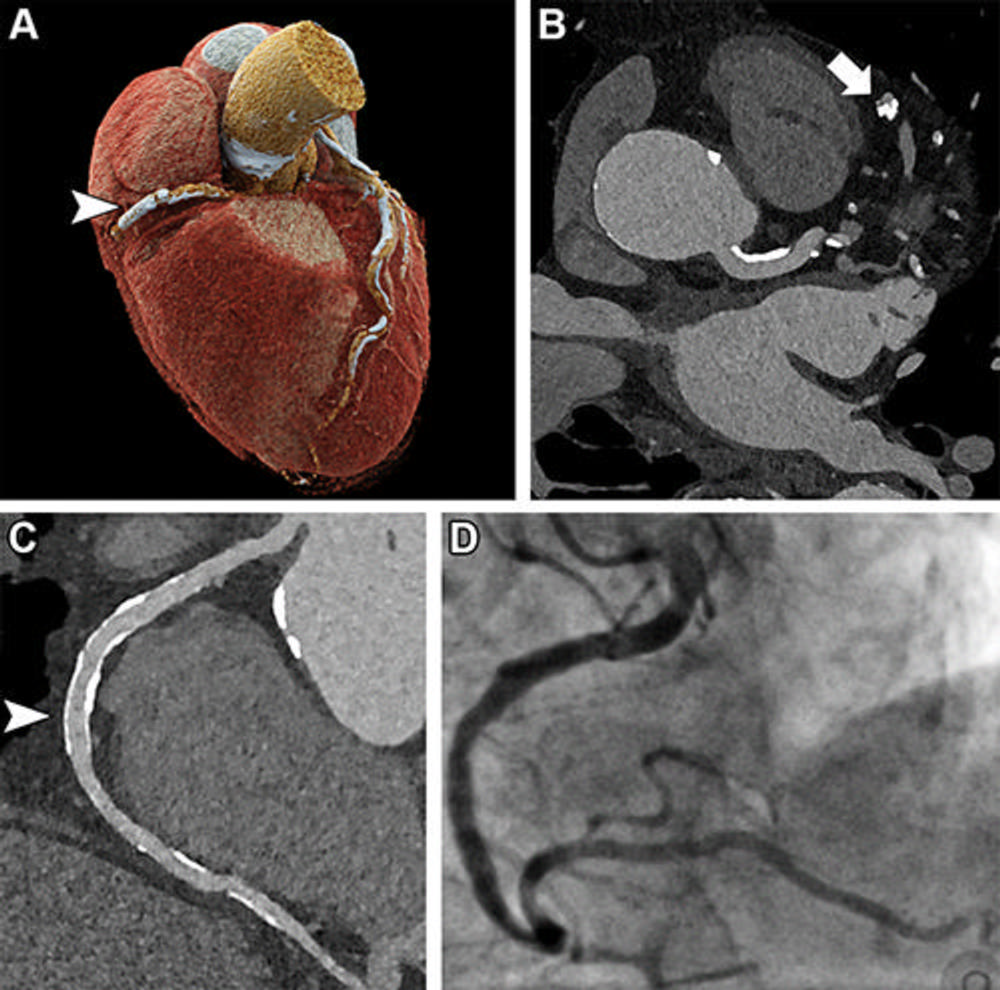

Figure 2. Ultrahigh-resolution (UHR) coronary CT angiography (CCTA) in an 85-year-old man before transcatheter aortic valve replacement. Despite a stent in the right coronary artery and very severe coronary sclerosis with an Agatston score of 4162, diagnostic visualization of the coronary arteries succeeded, and obstructive coronary artery disease was excluded on CT images. (A) Three-dimensional cinematic rendering of the heart. The stent (arrowhead) is visible in the middle segment of the right coronary artery. (B) UHR CCTA with 0.2-mm axial sections. The lumen (arrow) of the severely calcified distal left anterior descending artery can be assessed without artifacts. (C) Curved multiplanar reformations of the right coronary artery with a diagnostic display of the stent lumen (arrowhead). (D) Invasive coronary angiography enables exclusion of in-stent stenosis.